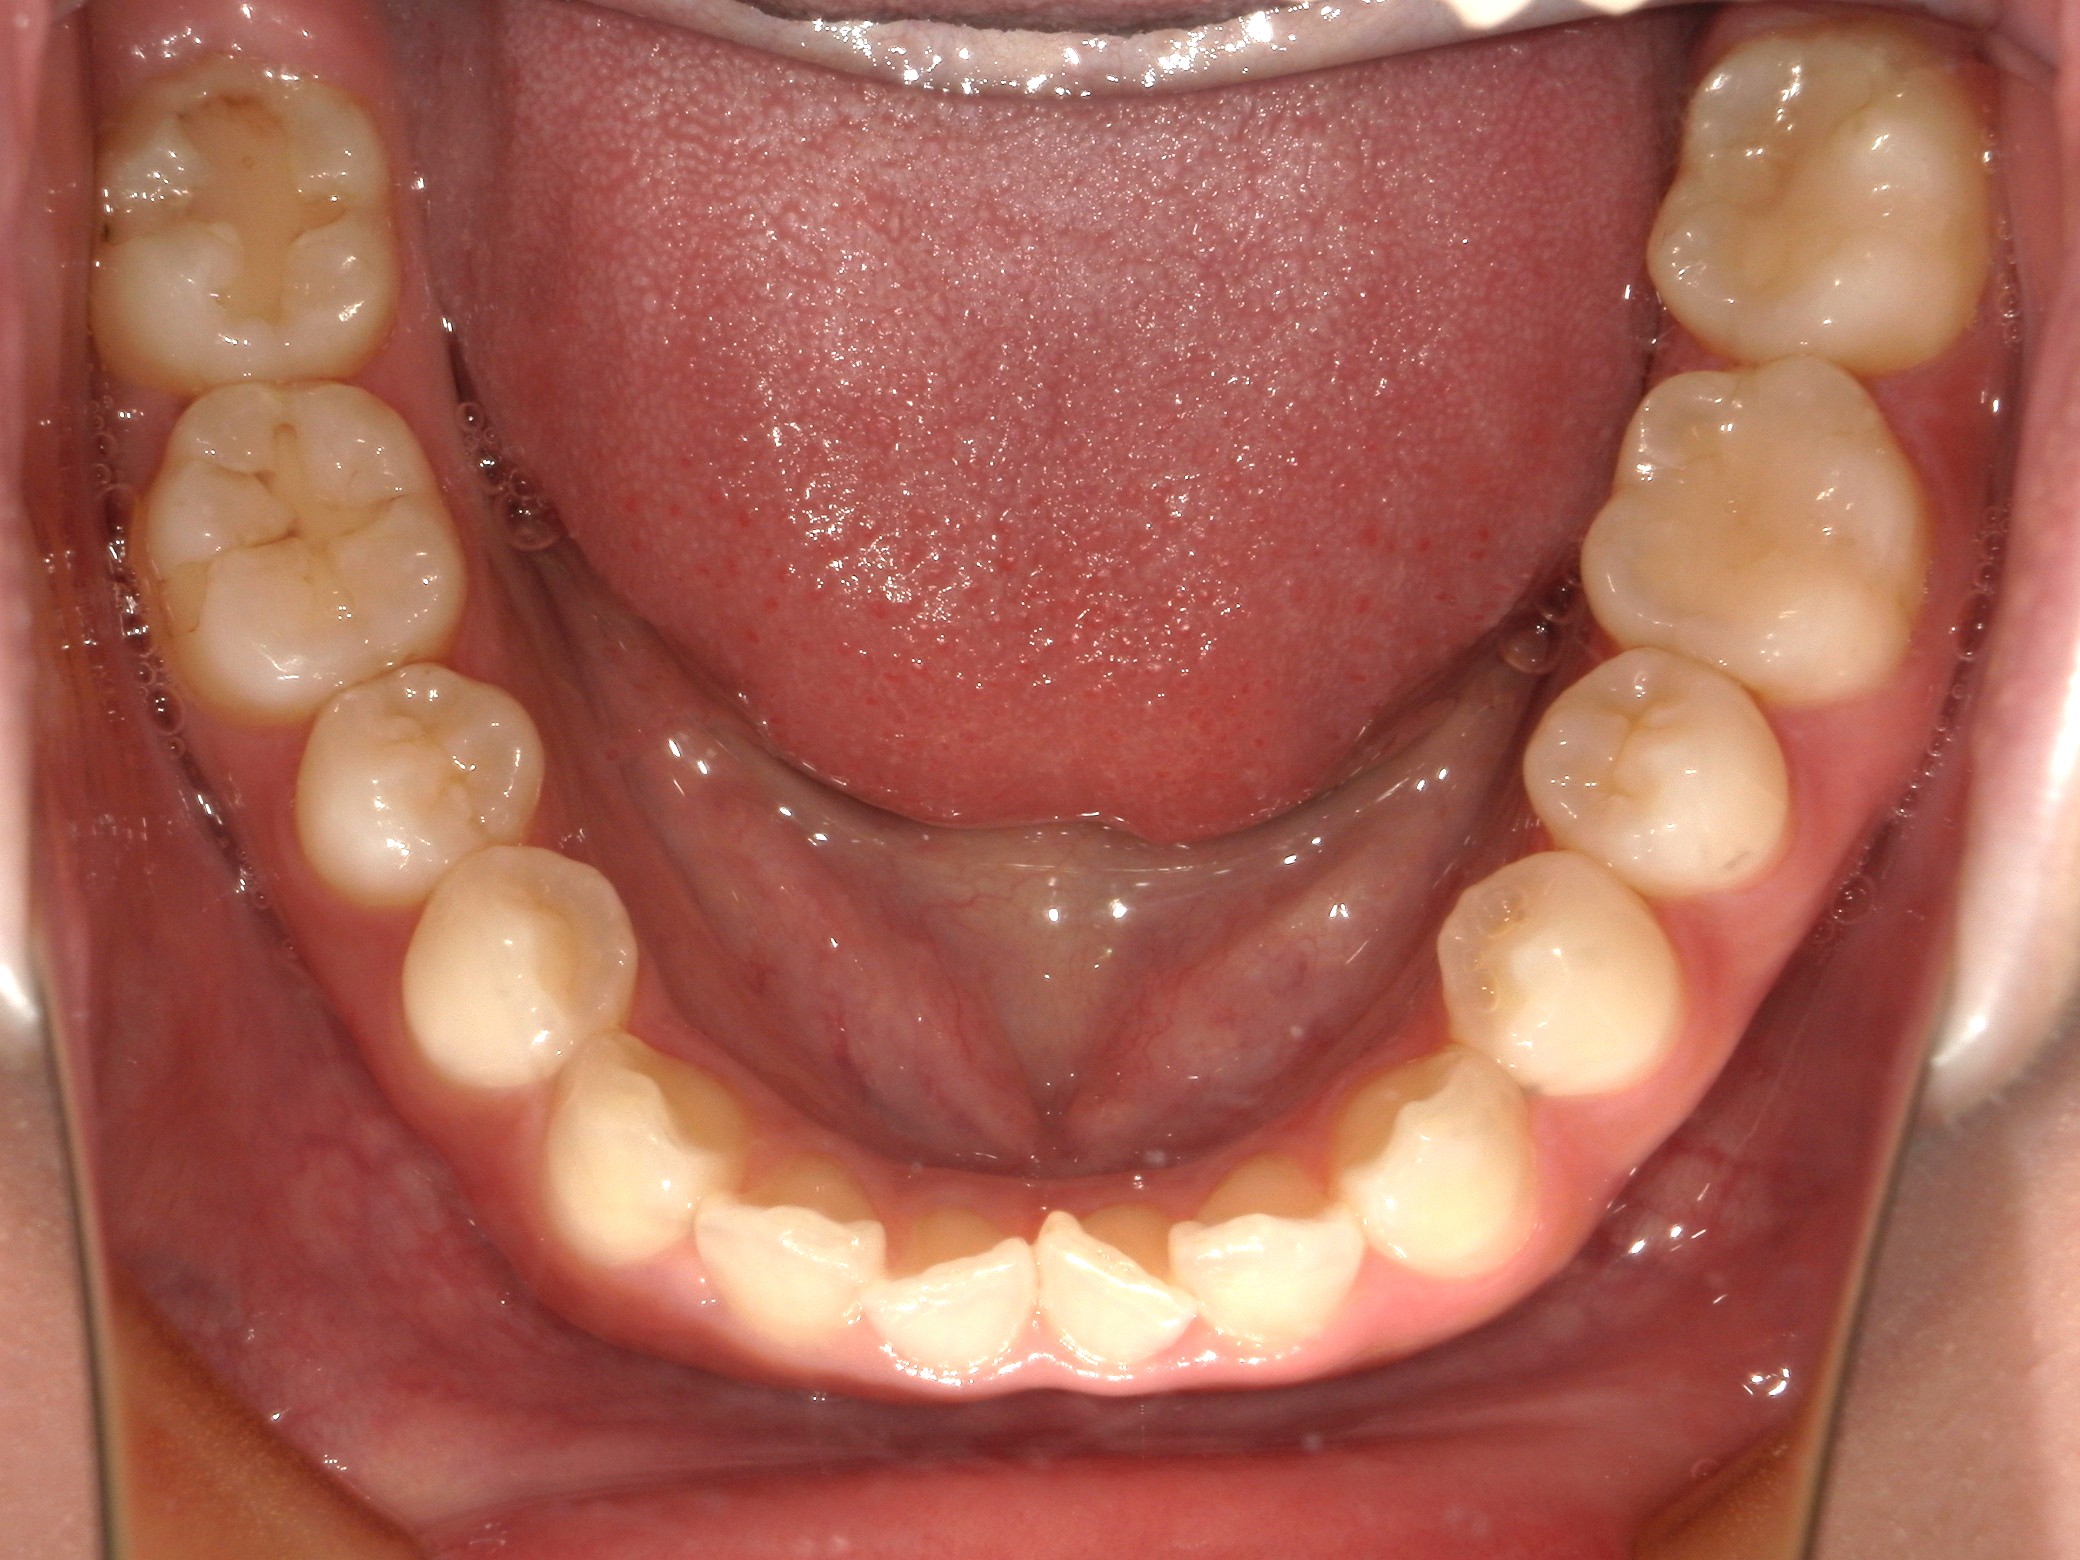

口内下

治療前

治療後